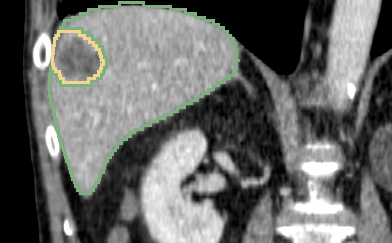

Refer to caption

Figure 7: The example liver lesion segmentation results from 3D AH-Net. The segmented contours of liver (blue) and liver lesion (pink) are overlaid on 3 slices viewed from different orientations (Axial, Coronal and Sagittal). The segmentations are rendered in 3D on the right.

The performance of AH-Net is listed in Table 5, together with other six top-ranked submissions retrieved from the LITS challenge leaderboard. These submissions employ various types of neural network architectures: 2D, 3D, 2D-3D hybrid, and model fusion. Two evaluation metrics are adapted: (1) Dice Global (DG) which is the dice score combining all the volumes into one; (2) Dice per Case (DPC) which averages of the dice scores of every single case. The Dice score between two masks is defined as DICE(A,B)=2|AB|/(|A|+|B|)𝐷𝐼𝐶𝐸𝐴𝐵2𝐴𝐵𝐴𝐵DICE(A,B)=2|A\cap B|/(|A|+|B|). Our results achieve the state-of-the-art performance in three of the four metrics, including the dice global score of the lesions, dice global and dice per case score of the livers, which proves the effectiveness of AH-Net for segmenting 3D images with diverse anisotropic resolution. Some example results are shown in Fig.7.